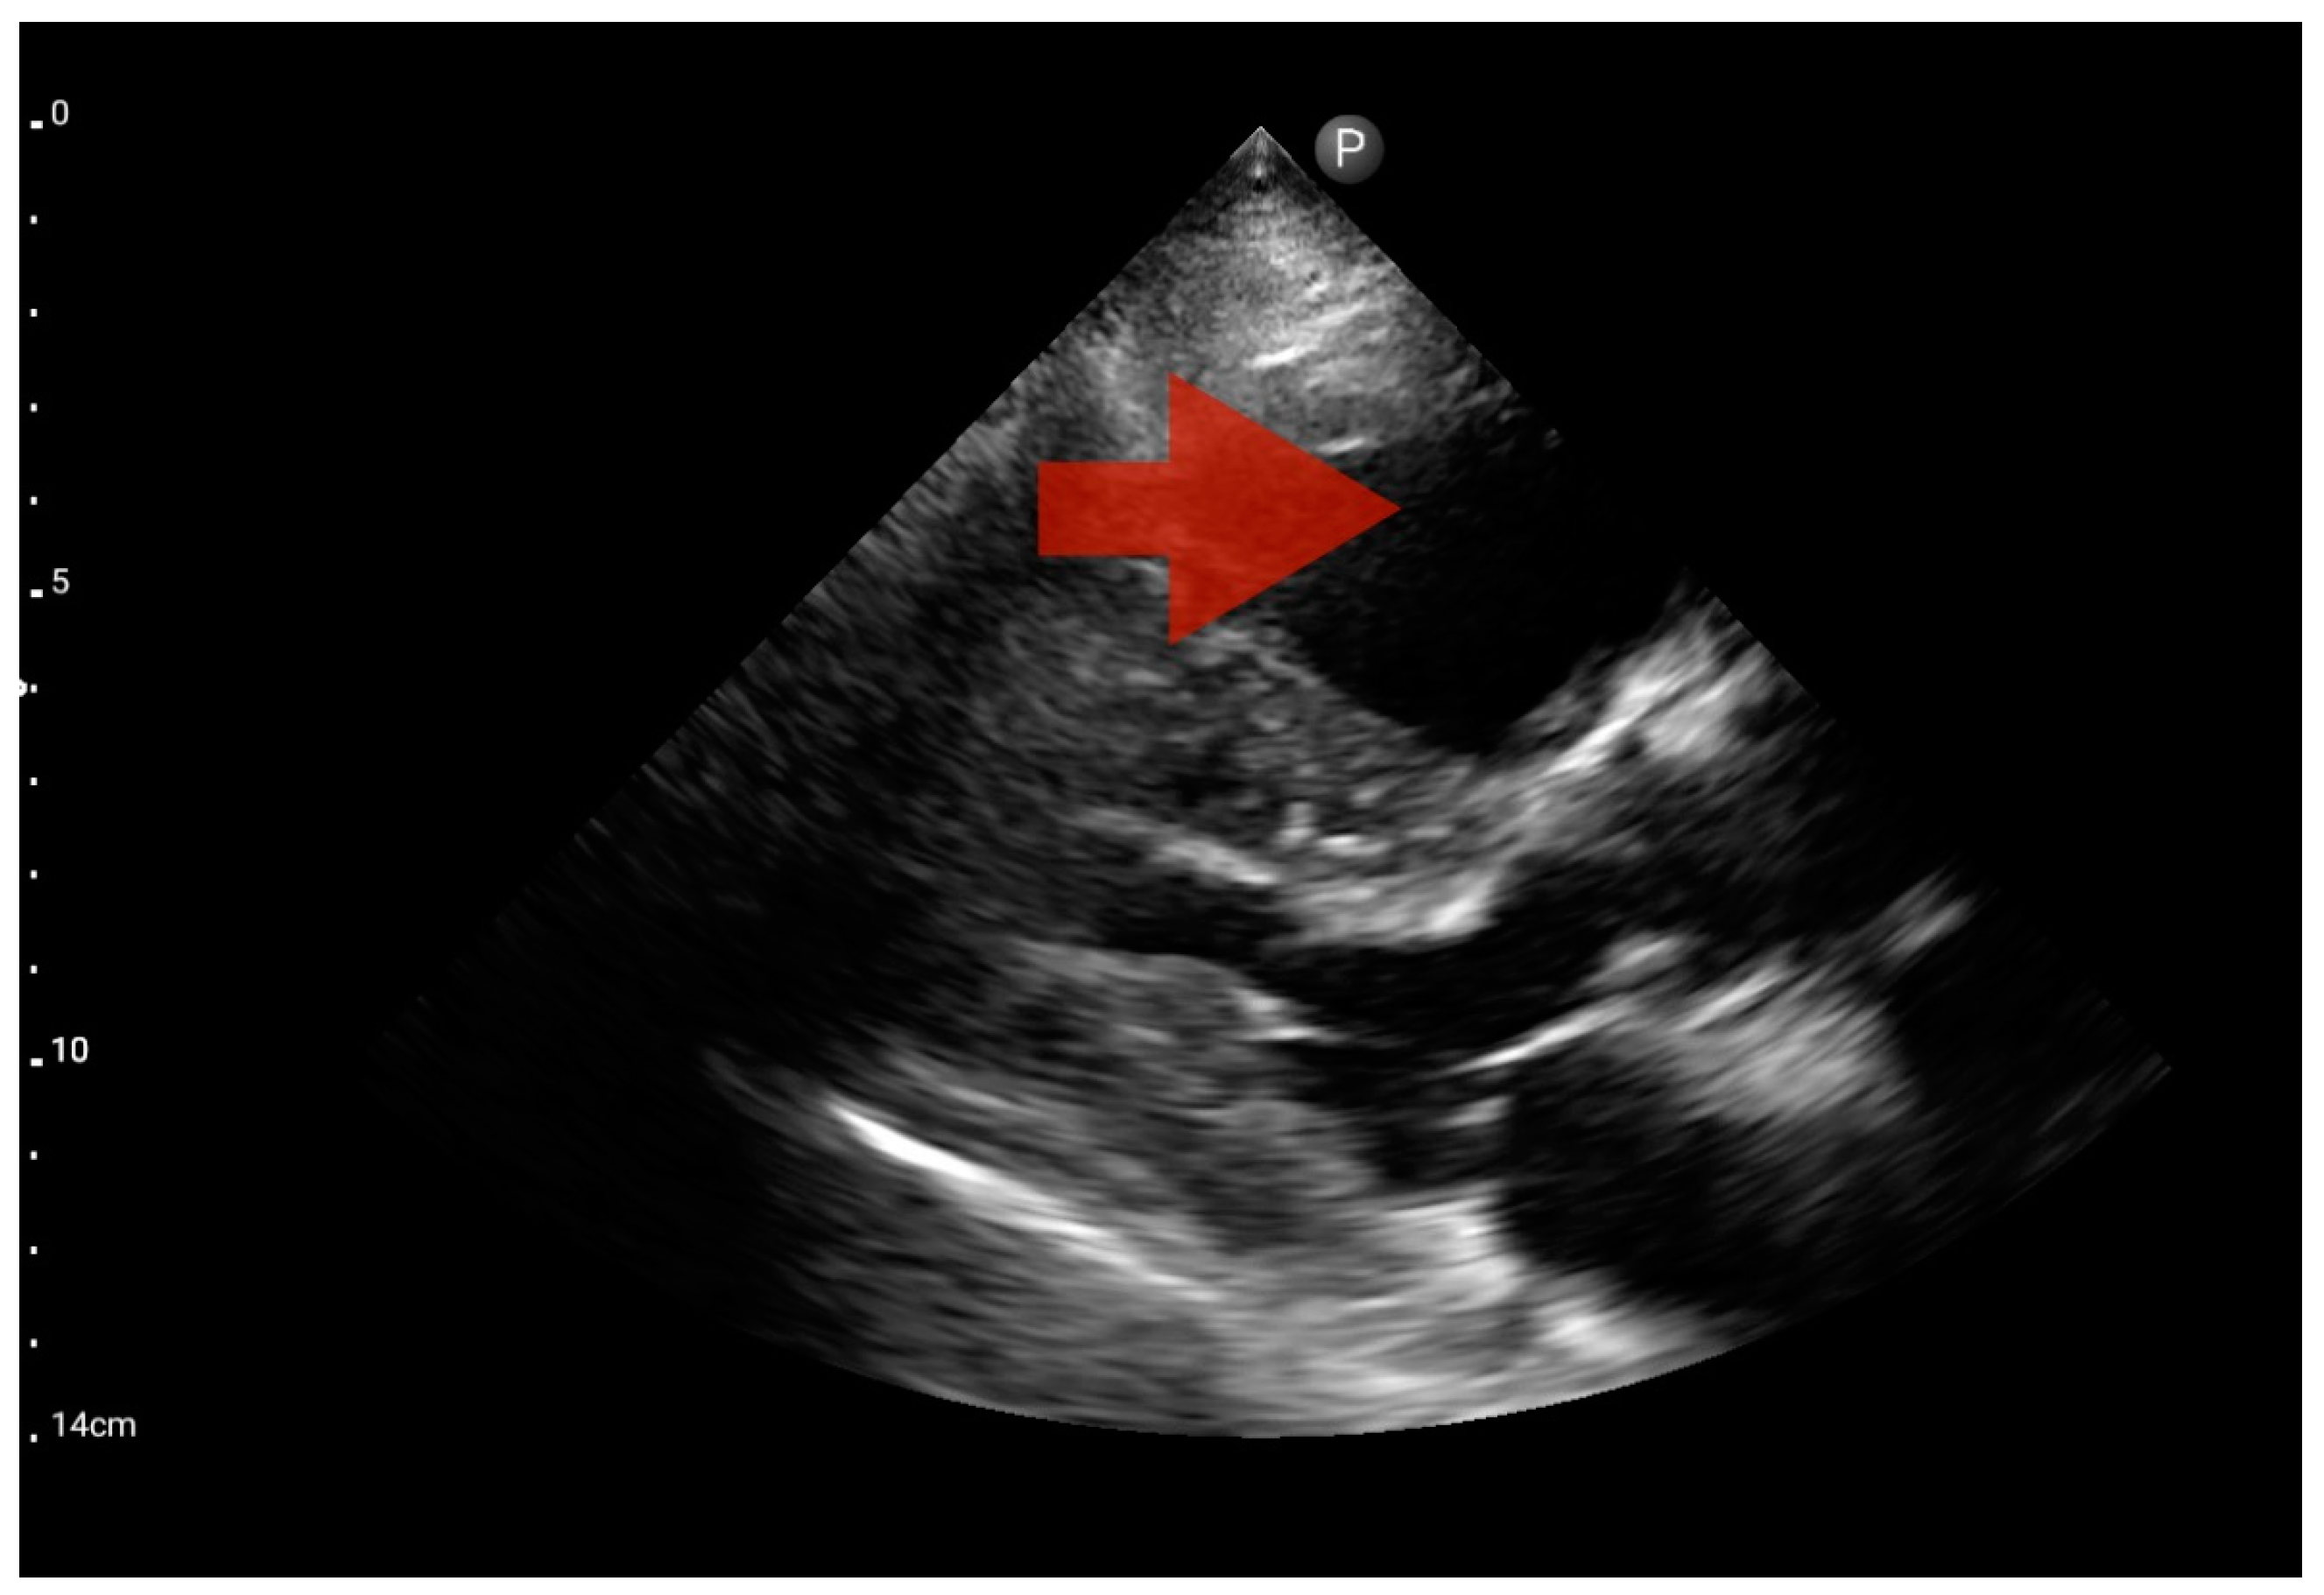

Other detected pathologies, including left ventricle enlargement (2 patients; 12.5%) (Figure 12), right ventricle enlargement (2 patients; 12.5%) (Figure 13) and pericardial effusion (1 patient; 6.25%) (Figure 14), were observed only incidentally. Therefore, further validation in a larger-scale study is warranted to analyze the significance of these symptoms in the pre-hospital setting.

Figure 14.

Pericardial effusion; position: apical four-chamber (FATE protocol). Sector probe; the red arrow indicates free fluid in the pericardium, which did not cause a sonographic image of cardiac tamponade (source: author’s material—DK).